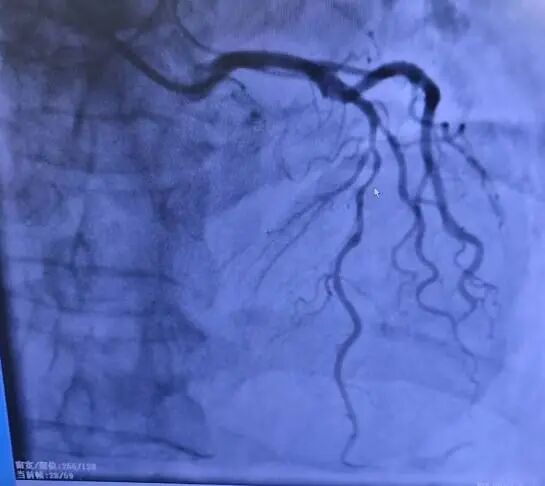

68岁的张大爷(化名)因反复胸痛、胸闷来院就诊。冠状动脉造影结果显示:前降支中段可见80%~90%狭窄伴有迂曲,此时介入治疗已非最佳选择,外科搭桥手术成为唯一出路。

鼠标所指位置为病变处